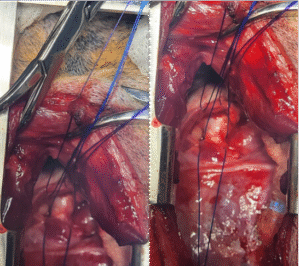

Nell was admitted to stay with us for two days. During surgery, her heart was approached through the left side of her chest. The abnormal vessel was carefully located and securely tied off.

Surgery photos showing the PDA being tied off!

One of the remarkable aspects of this condition is its very characteristic heart murmur. The moment the PDA is tied, that murmur disappears. For the surgical team, it’s an incredibly satisfying confirmation of success — an instant change you can hear.